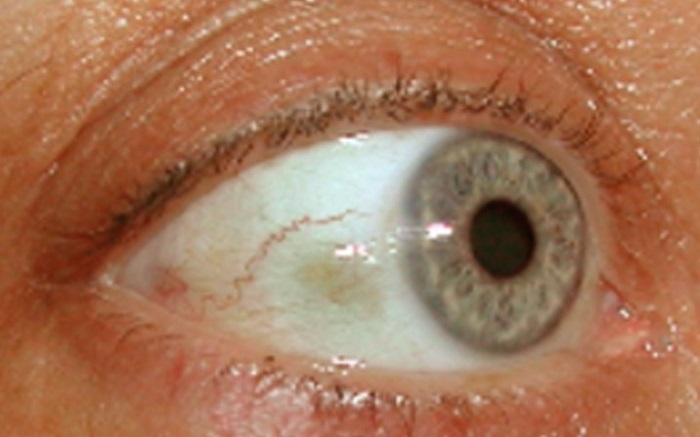

Bubble On Eyeball Causes And Treatment

https://www.healtholino.com/wp-content/uploads/2016/08/Bubble-on-Eyeball-–-Causes-and-Treatment.jpg